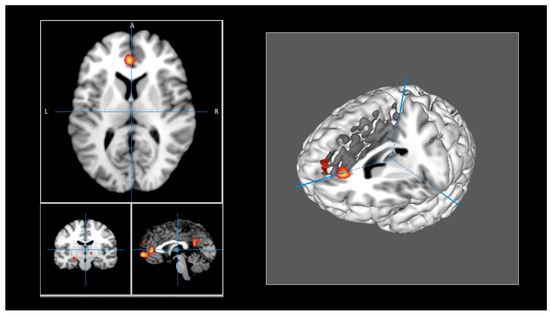

The brain regions identified in the meta-analysis are presented in Table 2. ALE maps were computed using GingerALE 3.0.2, at an FWE-corrected threshold of p < 0.05, with a minimum cluster size of K >150 mm3, and visualized using Mango (Figure 2). Eight activation clusters were found. One cluster included the left medial frontal gyrus and the left anterior cingulate (BA 10, 32). Other clusters were identified, including the left posterior cingulate (BA 23, 31), the left superior frontal gyrus (BA 9), and the anterior cingulate (BA 32). Another cluster was found in the left hypothalamus and the left medial globus pallidus. One cluster included the left parahippocampus (BA 35, 36) and parahippocampal structures, and another cluster was found in the left hippocampus and the lateral globus pallidus. Finally, the right thalamus, including the subthalamic nucleus, constituted another cluster of activation.

Figure 2. (Left panel): ALE maps were computed using GingerALE 3.0.2, at an FWE-corrected threshold of p < 0.05, with a minimum cluster size of K > 150 mm3, and visualized using Mango. (Right panel): Activations were projected onto a 3D rendering model of the brain.